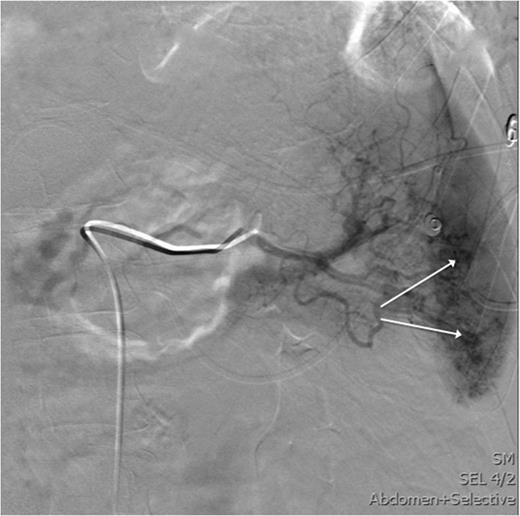

After the CT study, angiographic embolization of the splenic artery was performed. Angiographic catheter was inserted through the right femoral artery and guided into the splenic artery through the celiac trunk. The Spongostan (Ethicon Inc., Somerville, NJ, USA) particles were deployed to the branches of the splenic artery as the contrast leakage was seen in multiple locations. The proximal SAE with three Gianturco coils (Cook Medical Inc., Bloomington, IN, USA) and one Azur Peripheral HydroCoil (Terumo Medical Corporation, Somerset, NJ, USA) were deployed 4 cm distal to the celiac trunk (Figs 3 and 4). After the procedure, the patient was admitted to intensive care unit.

This image shows an angiography of the splenic artery observing splenic contrast leak (white arrows).